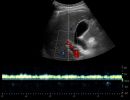

Με το Τriplex Σπληνοπυλαίου Άξονα αξιολογείται η πυλαία υπέρταση, συνήθως σε έδαφος χρόνιας ηπατοπάθειας και η βατότητα ή θρόμβωση της πυλαίας φλέβας και των ηπατικών φλεβών.